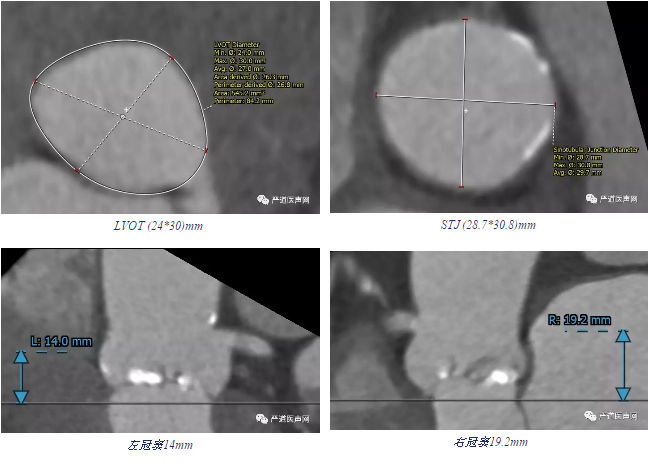

◆ 患者76岁女性,合并房颤,高血压,高血脂,慢性肾衰,风湿性心脏病。

◆ 三叶瓣,瓣环21.5*28.3mm,瓣周长79.7mm,面积485mm2,法式环36.6*35.6*34.2mm。

◆ 瓣叶增厚严重,钙化轻,瓣膜固定难度大,容易出现向左室流出道方向移位。

◆ 分别选取瓣上2mm, 4mm, 6mm, 8mm四个平面进行测量:

◆ 评估入路后最终选择予以经左侧颈动脉路径,便于更好操控输送器,稳定瓣膜位置。

◆ 根据瓣环尺寸及瓣上多平面测量结果予以25mm球囊扩张后经左颈动脉植入29mm的Venus-A瓣膜,结果满意。